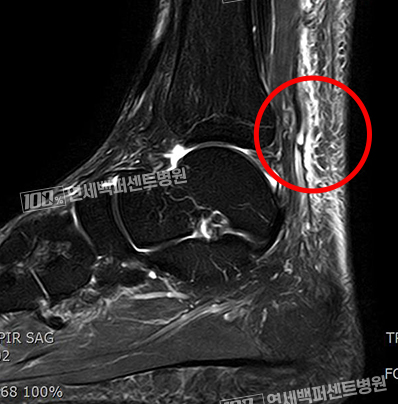

수술 전 MRI 영상

완전히 파열되어 절단된

아킬레스건